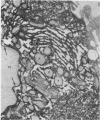

A knowledge of the biological characteristics of carcinogen-induced hyperplastic nodules of rat liver may be important in the understanding of cancer development. Although its biological role remains to be elucidated, the level of microsomal epoxide hydrase (epoxide hydrolase, EC 3.3.2.3) is 5- to 7-fold greater in hyperplastic nodules nodules induced by feeding the hepatocarcinogen 2-acetylaminofluorene than in liver of control rats. After removal of the carcinogen from the diet, the high level of the enzyme is maintained in those nodules that persist and in the hepatocellular carcinomas that subsequently develop. The availability of antibody to the epoxide hydrase made it possible to use electron microscopic immunocytochemistry to localize this enzyme in the cells of hyperplastic nodules. The immunocytochemical procedure provides direct visual evidence for the presence of this enzyme in smooth endoplasmic reticulum and also in rough endoplasmic reticulum (including the nuclear envelope) of the nodule's parenchymal cells.